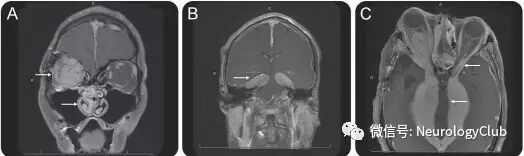

图1:特发性肥厚性硬脑膜炎患者;可见肥厚的硬脑膜在T2WI(a,e)上呈低信号,FLAIR(b)和DWI(f)上亦为低信号;T1增强(c,d)可见硬脑膜(左侧>右侧)明显不对称性强化;左侧小脑幕处硬脑膜中心线样无强化,两侧周边轨道样强化,即“轨道征”

图9:IgG4相关性肥厚性硬脑膜炎患者;A:T1增强可见鼻咽部和眼眶炎性假瘤形成;B:小脑幕弥漫增厚强化,形成瘤样肿块;C:肥厚性硬脑膜炎侵入眼眶,中脑和视神经明显受压

图10:IgG4相关性肥厚性硬脑膜炎患者;A-B:T1增强可见左侧额区不均匀强化的不规则脑外肿块(其实为肥厚性硬脑膜);邻近胼胝体和扣带回亦可见强化病灶(黑箭);C-D:T2WI可见病灶附件广泛脑水肿